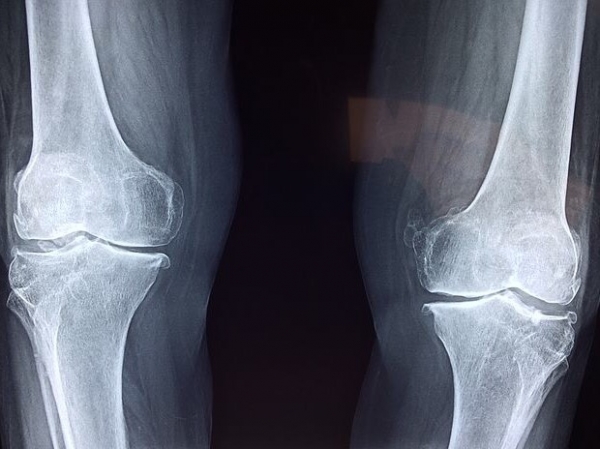

류마티스 관절염은 연골의 퇴행에 의한 관절염이 아니라 몸 안의 면역세포가 자기 자신의 관절 조직을 스스로 공격해 파괴시키는 자가면역질환이다. 자가면역반응은 한번 생기면 계속 지속되는 경우가 대부분이라서 평생 치료해야 한다. 주로 작은 관절인 손가락, 발가락, 손목, 발목 관절을 공격하지만 턱 관절, 무릎관절, 어깨 관절, 목 관절 등 모든 관절을 공격하며 관절 이외에도 폐, 혈관, 심장 등에도 염증이 생길 수 있다.

관절에 통증이 생긴다는 점은 같다. 하지만 퇴행성 관절염은 관절을 많이 사용했을 때 통증이 생기기 때문에 활동을 시작하면 더 악화되고 류마티스 관절염은 활동을 하면 통증이 줄어든다는 특징이 있다. 두 관절염 모두 이른 아침에 관절이 뻣뻣해지는 조조강직이 있지만 류마티스 관절염은 여러 관절이 동시에 붓는다는 특징이 있다. 만약 자고 난 이른 아침에 뻣뻣함과 함께 통증이 1시간 이상 지속되고 관절 마디마디가 많이 부어 오른다면 류마티스 관절염 등 염증성 관절염을 의심해 봐야 한다.